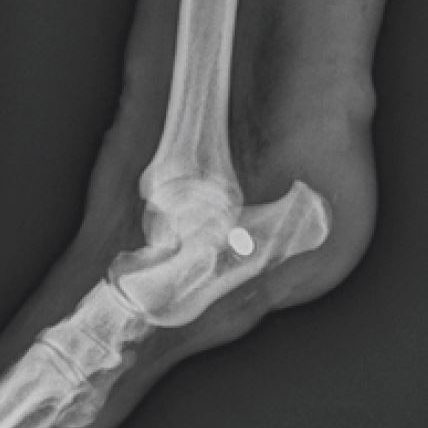

Gastrocnemius Tendon Reconstruction Under Construction. Share this post Share on FacebookShare on Facebook TweetShare on Twitter Pin itShare on Pinterest Share on LinkedInShare on LinkedIn Share on WhatsAppShare on WhatsApp Project navigationPreviousPrevious project:Tarsus Medial Collateral LigamentNextNext project:Elbow